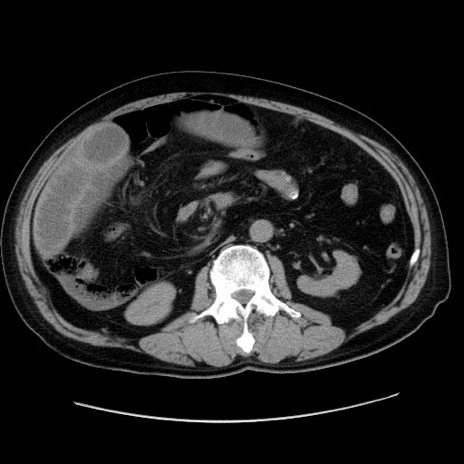

症例30(横断像)

冠状断像

【症例】80歳代男性

【現病歴】約6時間前から臍下部痛が出現。次第に腹部膨隆・背部痛も生じてきたため来院。背部痛の場所は変化しない。

【身体所見】意識清明、BT 36.3℃、BP  131/87mmHg、P 87bpm、SpO2 100%(RA)、臍周囲自発痛・圧痛あり、反跳痛なし、自発痛部位に一致して板状硬あり、腹部膨隆、腸雑音減弱、CVA tenderness両側陰性。